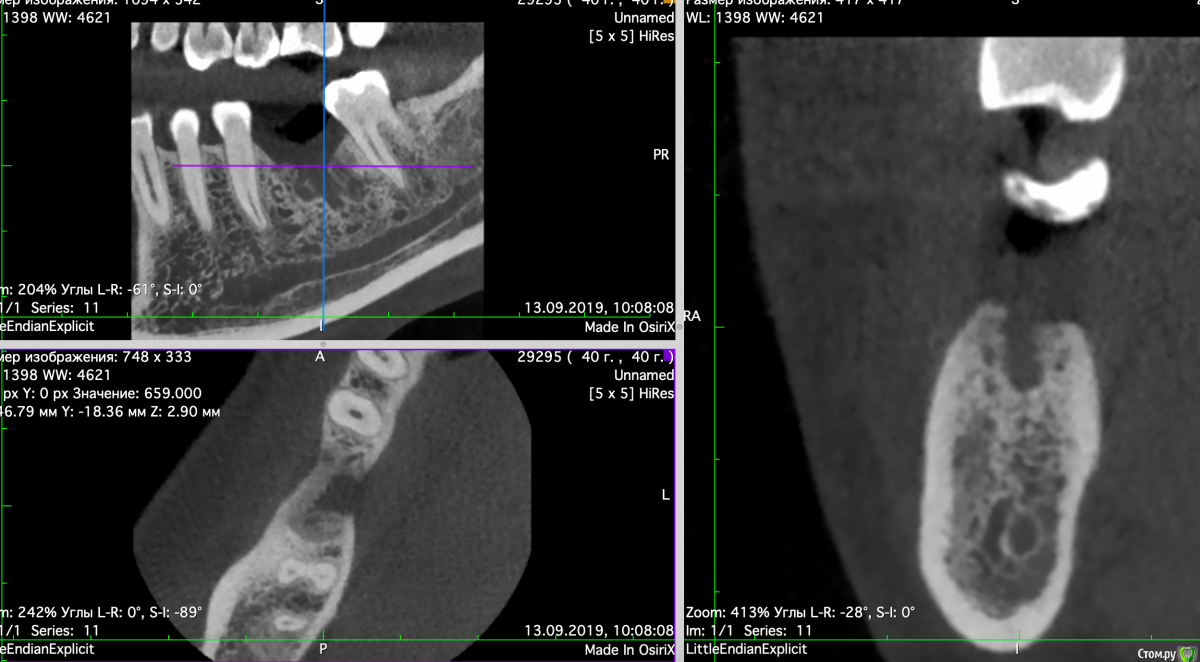

Valerkaa Опубликовано 13 сентября, 2019 Поделиться Опубликовано 13 сентября, 2019 Добрый день, коллеги. Помогите, пожалуйста, советом. Планируется имплантация, удаление было в феврале. Смущает состояние кости. Понятно, что можно раскрыться, и если грануляции, то кюретаж. Просто морально хочется понимать, чего ждать. Была ситуация, когда с похожей картиной на КТ раскрылась, кость была визуально норм, но через месяц имплант просто пинцетом достала.Собственно вопрос: нормальное ли это состояние кости через полгода после удаления или все-таки что-то не так и надо морально готовиться к кюретажу? Опыт в имплантации совсем небольшой, поэтому такие вопросы возникают)) Ссылка на комментарий

Евгений Ходыкин Опубликовано 13 сентября, 2019 Поделиться Опубликовано 13 сентября, 2019 Будет кюретаж, всё верно. 2 Ссылка на комментарий

dr Alexandr Опубликовано 14 сентября, 2019 Поделиться Опубликовано 14 сентября, 2019 Нужен кюретаж, что б потом не готовиться морально к удалению имплантанта!..подготовить кость и спланировать операцию, возможно понадобиться подсадка кости. Ссылка на комментарий